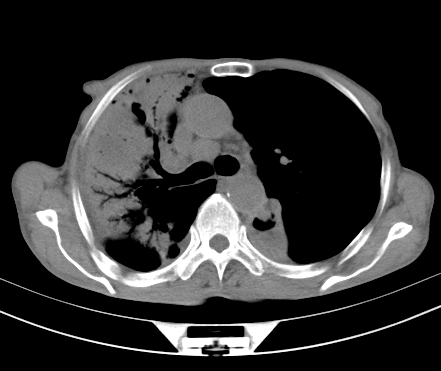

以下是引用gaoshengjiang在2008-5-30 19:53:00的发言:[br]右上叶可见大片实变影,其内可见充气支气管影及囊状影,右上叶尖端支气管走形区可见结节样影,左侧胸腔内可见胸腔胃影。纵隔淋巴结肿大。[br]考虑:1.右上肺阻塞性肺炎伴肺脓肿形成。支持转移所致。[br] 2.左侧胸腔胃。